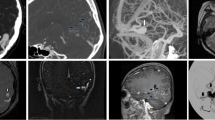

Case 1 (false positive, Fig. 2): the 4D-CTA of a 52-year-old female, presenting with tinnitus, suggested a Borden-type I dAVF. 4D-CTA image quality was good with the diagnosis being considered sufficiently certain. It showed early venous filling in the late arterial phase in the right hemisphere which was not reproduced by DSA.

Case 2 (misclassification, Fig. 3): the 4D-CTA of a 59-year-old male, presenting with headache, was of poor image quality and showed early venous filling and appeared to demonstrate a bAVM, as an abnormal vascular pattern suggested the presence of a nidus. The 4D-CTA diagnosis was considered to be sufficiently certain. However, DSA demonstrated a Borden-type I dAVF.

Case 3 (false negative, Fig. 4): the 4D-CTA of a 29-year-old female, presenting with hemorrhage, was of good image quality and did not demonstrate an abnormality, although significant doubt was noted. DSA demonstrated a micro-AVM (< 3 cm) with multiple draining veins.

Case 4 (false negative, Fig. 5): the 4D-CTA of a 31-year-old male, presenting with a seizure, was of moderate image quality and could not demonstrate an AV shunt. Significant doubt was noted and DSA subsequently demonstrated a Borden-type III dAVF.

Panels a and b (right external carotid artery injection) are from the case where a false-negative 4D-CTA missed a dAVF. The DSA demonstrates a small transosseous dural branch from the occipital artery (arrowheads) feeding a Borden-type 3 dAVF (asterisk). The arrow depicts the arterialized draining vein. Some of these structures are partly seen in the 4D-CTA study, but their significance is unclear